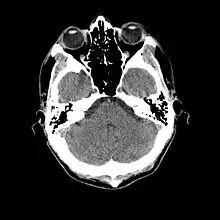

- 1976

- Cranial computed tomography (CT, invented 1972) proved to be an excellent tool for diagnosing cerebral neoplasms in children, including those found in tuberous sclerosis.[46]

- 1987

- MR was judged superior to CT imaging for both sensitivity and specificity. In a study of fifteen patients, it identified subependymal nodules projecting into the lateral ventricles in twelve patients, distortion of the normal cortical architecture in ten patients (corresponding to cortical tubers), dilated ventricles in five patients, and distinguished a known astrocytoma from benign subependymal nodules in one patient.[53]

- 1987

- MR imaging was found to be capable of predicting the clinical severity of the disease (epilepsy and developmental delay). A study of 25 patients found a correlation with the number of cortical tubers identified. In contrast, CT was not a useful predictor, but was superior at identifying calcified lesions.[54]

- Cortical tubers found on MR imaging corresponded exactly to the location of persistent EEG foci, in a study of six children with TSC. In particular, frontal cortical tubers were associated with more intractable seizures.[56]